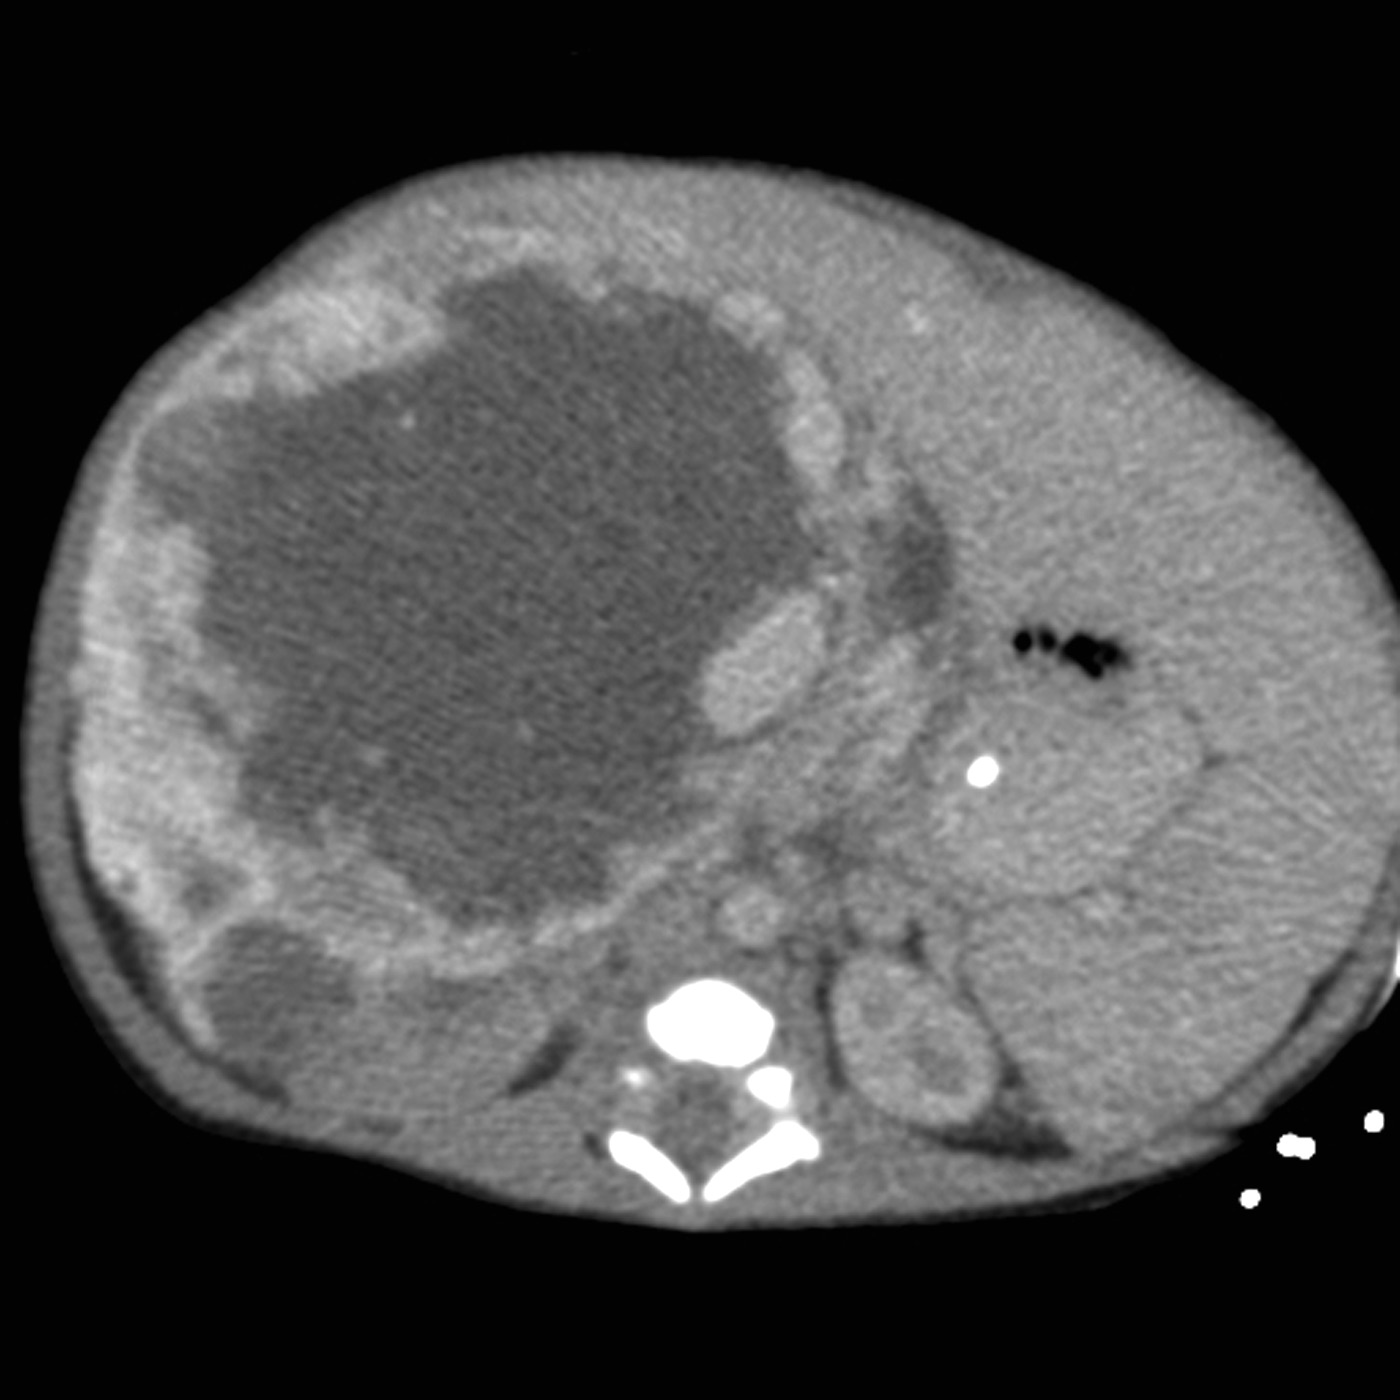

The radiograph showed a large radiopaque mass that encompassed most of the right and left upper quadrants, with multiple loops of bowel displaced into the pelvis, a paucity of bowel gas, and low lung volumes. Abdominal CT revealed a heterogeneous mass with origin in the right lobe of the liver and contact of the left tip of the liver with the spleen (Figure 1). Further evaluation with MRI showed a heterogeneous mass of 8.8 × 6.9 × 8.4 cm with peripheral enhancement and large, nonenhancing areas centrally (Figure 2).

Figure 1 – This abdominal CT slice shows a heterogeneous mass with origin in the right lobe of the liver and contact of the left tip of the liver with the spleen.